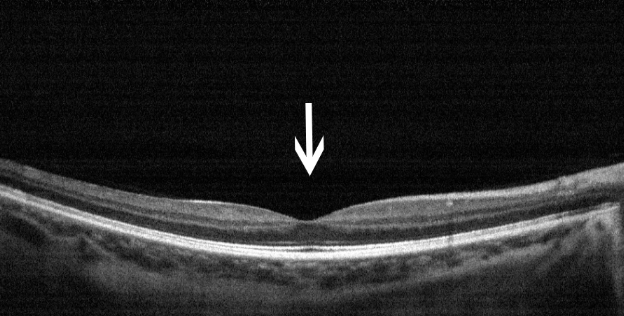

5 视网膜脱落

病因:视网膜神经上皮层脱落。

治疗:需及时进行玻璃体视网膜手术。